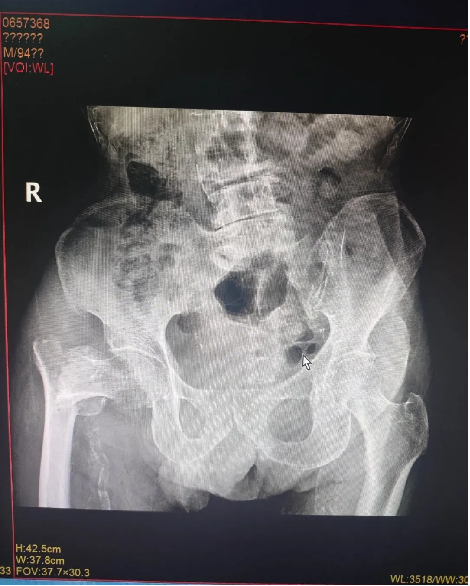

近日,医院成功为97岁高龄患者实施右股骨粗隆间骨折闭合复位髓内钉内固定术(PFNA)。

患者余某,男性,97岁高龄,因在家不慎摔伤致右股骨粗隆间骨折住院治疗,入院诊断:右股骨粗隆间骨折,中度贫血,严重营养不良,严重骨质疏松,低钾血症,脑梗死后遗症,高血压病,慢支肺气肿。创伤骨科在接诊后,迅速为患者开通“高龄骨折绿色生命通道”,组织心血管内科、呼吸内科、营养科、麻醉科等多学科会诊后,全面评估病情、严格把控围手术期各项指标,精心定制手术方案与术后风险预案,经与患者及家属沟通同意手术后,在椎管内麻醉下行“右股骨粗隆间骨折闭合复位髓内钉内固定术”,经多学科协作在患者入院48小时内最佳手术窗口期完成手术,术后指导功能锻炼,最大可能避免了老年髋部骨折如血栓,压疮,坠积性肺炎等致命性并发症,患者入院治疗10天后康复出院。患者及家属对医院的医疗水平给予了高度的肯定,对医护人员的辛勤付出表达了衷心的感谢!